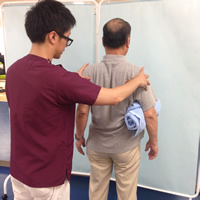

2.リハビリテーション

腱板修復術後のリハビリでは、肩関節以外に肩甲骨など他部位の柔軟性も非常に重要となります。

入院中のリハビリは、痛みや炎症の悪化を考慮し肩甲骨や肘のストレッチなど、肩関節以外の治療が中心となります。

ただし患者さんによっては痛みのない範囲で理学療法士が手術した肩を動かす場合があります。

術後約3週間の装具固定期間が過ぎると、徐々に肩関節ならびに肩甲骨の動きの改善を図ります。

手術後3週目の様子です。 装具を外した状態でのリハビリを開始していきます。 |

手術後2~3ヶ月目の様子です。 徐々に肩の筋肉強化を図っていきます。 |

手術後6ヶ月以降の様子です。 仕事・スポーツ復帰に向けてトレーニング強度を上げていきます。 |